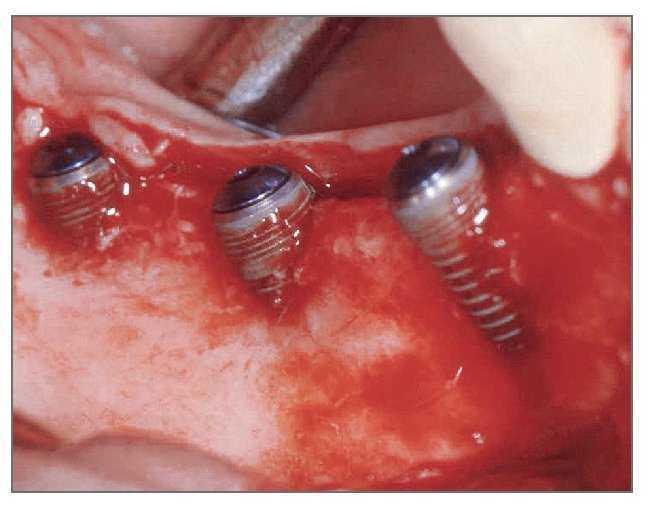

El paciente se enjuagó con colutorio de clorhexidina al 0,12% (Hexamedine, Bukwang) durante 2 min antes de la operación. Después de aplicar anestesia local con lidocaína al 2% y epinefrina 1:100.000, se levantó un colgajo de espesor total, poniendo de manifiesto el defecto óseo del alveolo vestibular. La dehiscencia vestibular era de 2,0 a 6,0 mm apicoronalmente. Se colocaron tres implantes de 3,8 x 12,0 mm (Implantium, Dentium) en el área molar de la mandíbula derecha con un torque de inserción de 40 Ncm (fig. 2). El defecto remanente y los vacios marginales se injertaron con hueso bovino deproteinizado (Bio-Oss, Geistlich Pharm) (fig. 3). Se empleó MDA para cubrir completamente el injerto óseo y asegurarlo bajo los colgajos vestibular y lingual (fig. 4). A continuación, se reposicionó el colgajo y se cerró la herida con suturas simples (Ethicon, Johnson & Johnson Medical).

Figura 4 (izquierda). Se modeló el MDA para cubrir completamente el defecto y el injerto óseo.